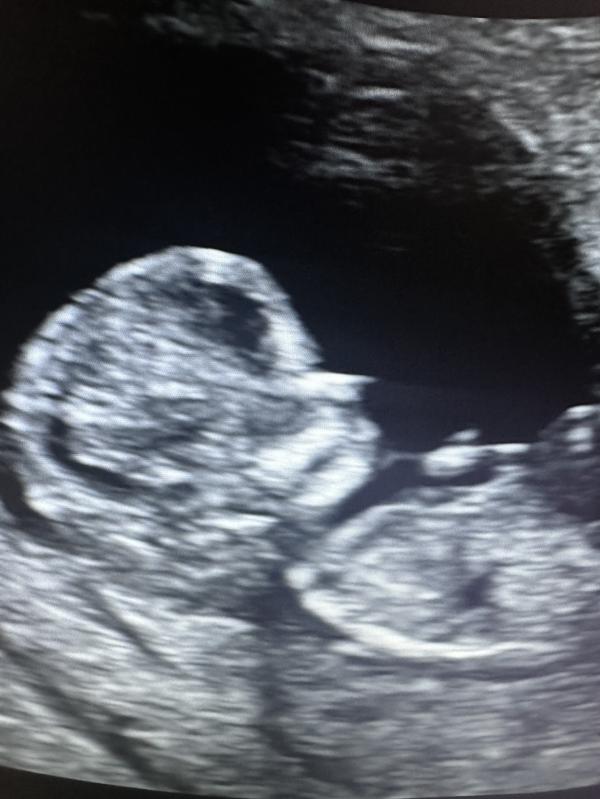

Всем привет! Время летит очень быстро! Посмотрела, последний пост мой еще с колечком на узи, а тут уже полноценный человек.

1 скрининг пройден, НИПТ тоже. Все отлично! И…полный комплект, у нас будет доченька🥰 сын о ней мечтал и муж мечтал. Хотя у него уже два парня от первого брака и шансы были ну очень малы. Ни родным, ни друзьям, ни сыну пока не сообщали -хочется максимально поздно это сделать.

Весит красотка 273 грамма. Срок ПДР сдвинут на 28 августа.